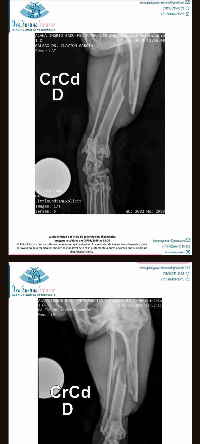

Oi, me chamo Alanna e sou tutora do Badu , que no momento precisa de um custo alto para pré op+ cirurgia. Badu tem 10 anos , idoso, amoroso , dócil e carinhoso, há dois dias sumiu de minha residência e voltou todo sujo e machucado. Infelizmente foi mais um nas mãos da crueldade humana . Levei ao Vet, foi examinado e realizado RX onde foi observado a fratura grave em fêmur, possívelmente causado por uma Paulada. Badu já havia sofrido um chute nessa mesma pata anos atrás, que prejudicou sua macha e apoio 100%. Necessito de ajuda pois sozinha n consigo cobrir os custos, e infelizmente o caso só se resolve com cirurgia . Ficaria extremamente grata e meu velho amigo também ♥️